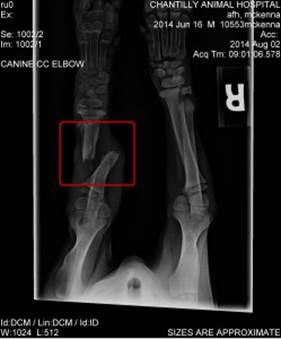

One of her legs was completely broken through (as seen in her x-ray). Of course, we immediately took her to our vet to be examined, and we were told that there is no way that the break would have healed by itself. McKenna needed surgery.

McKenna xrayNot only was the leg broken, but there was a break in the growth plate too. The growth plate is an opening at the ends of a dog’s bones that allow the bones to become longer until the dog is fully grown. Damage to the growth plate can cause stunted growth.

We asked the vet her opinion on how she thought McKenna was injured and her guess was that she was either thrown from a car or kicked with a lot of force – in other words – blunt force trauma.

McKenna’s leg was recently amputated. This is still an active, happy little girl. To date we have spent almost $8,000 on McKenna’s care. If you would like to help pay for her care, please visit https://www.crowdrise.com/fundraiser/edit/mckennathepuppy/afh2002 or send your check to: